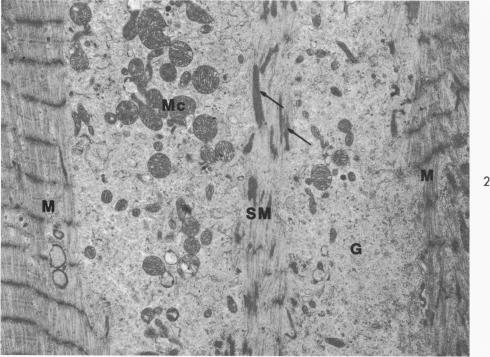

The fine structure alterations in the atrium and atrial appendage, mitral valve and papillary muscle are described in 11 matched patients with chronic rheumatic heart disease. The muscle changes consisted of loss of myofilaments and accumulation of lipid and osmiophilic dense bodies. The connective tissue stroma of the atrium and the mitral valve showed extensive deposition of collagen and elastic fibers. There were numerous foci of collagen degeneration, characterized by fraying of the collagen fibers and accumulation of homogeneous granular material at these sites. Although the muscle changes were more striking, the connective tissue alterations appear important in the evolution of the chronic disease. The extent of collagen degeneration appeared to parallel the degree of collagen formation. The muscle fiber degeneration and connective tissue alterations did not correlate with the clinical findings. At the resolution of the electron microscope, the continuing process in the rheumatic heart appears to be primarily collagen formation and degradation rather than primary degeneration of the muscle fibers. It is the balance of these processes which determine the clinical state of the patient. Acute muscle damage along with evidence of inflammation do not seem to be associated with progressive, chronic rheumatic heart disease.

在11例匹配的慢性风湿性心脏病患者中,描述了心房、心耳、二尖瓣和乳头肌的精细结构改变。肌肉变化包括肌丝丧失以及脂质和嗜锇致密小体的积聚。心房和二尖瓣的结缔组织基质显示出大量胶原纤维和弹性纤维的沉积。有许多胶原纤维变性灶,其特征为胶原纤维磨损以及在这些部位有均匀颗粒物质的积聚。虽然肌肉变化更为显著,但结缔组织改变在慢性疾病的发展过程中似乎也很重要。胶原纤维变性的程度似乎与胶原形成的程度平行。肌纤维变性和结缔组织改变与临床发现无关。在电子显微镜下观察,风湿性心脏病的持续过程似乎主要是胶原形成和降解,而非肌纤维的原发性变性。正是这些过程的平衡决定了患者的临床状态。急性肌肉损伤以及炎症证据似乎与进行性慢性风湿性心脏病无关。